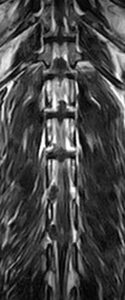

犬の多発性胸腰部椎間板ヘルニアのMRI検査

市外の先生からダックスちゃんの腰の痛みの精査依頼でMRI検査のご紹介がありました。検査結果から多発性胸腰部椎間板ヘルニアを認めました。その後かかりつけの先生のもとで内科治療となりました。